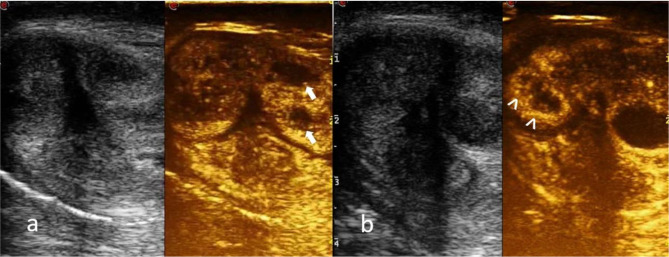

Fig. 6.

a CEUS shows two abscesses in the left corpus cavernosum (arrow); b CEUS identificates two small abscesses in the right corpus cavernosum not evident in the basal evaluation (arrowhead)